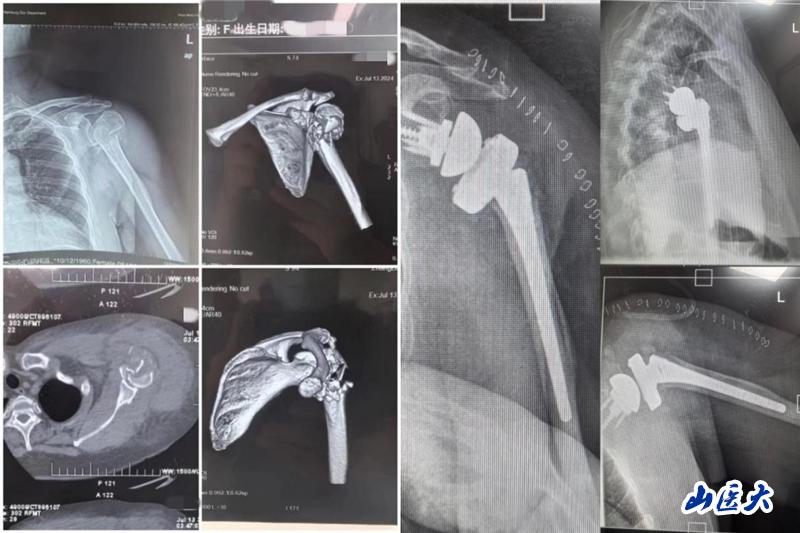

7月24日,我校第二医院骨科脊柱创伤病区肩肘创伤团队成功独立完成第二医院首例肱骨近端粉碎性骨折反向肩关节置换术,标志着医院在肩关节疾病诊疗领域迈出了重要的一步,弥补了在该领域的技术空白,为今后开展更多此类手术奠定了基础。

患者是一位63岁女性,主因车祸致左肩关节疼痛、肿胀伴活动受限就诊,完善相关检查结果示:左肱骨近端粉碎性骨折。栗树伟副主任医师团队多次进行术前病例讨论,综合患者年龄较大、骨折类型为严重肱骨近端粉碎性骨折、肩关节功能严重受损等因素考虑,本着最大程度提高患者生活质量的医疗服务理念,决定为患者实施反向肩关节置换术。

术后的精心护理对患者的恢复也至关重要,护理团队耐心、细心、用心地护理和交流让患者充分感受到关爱与温暖。目前,患者术后拍片假体安置满意,切口愈合佳,肩关节功能恢复良好,现已顺利出院。